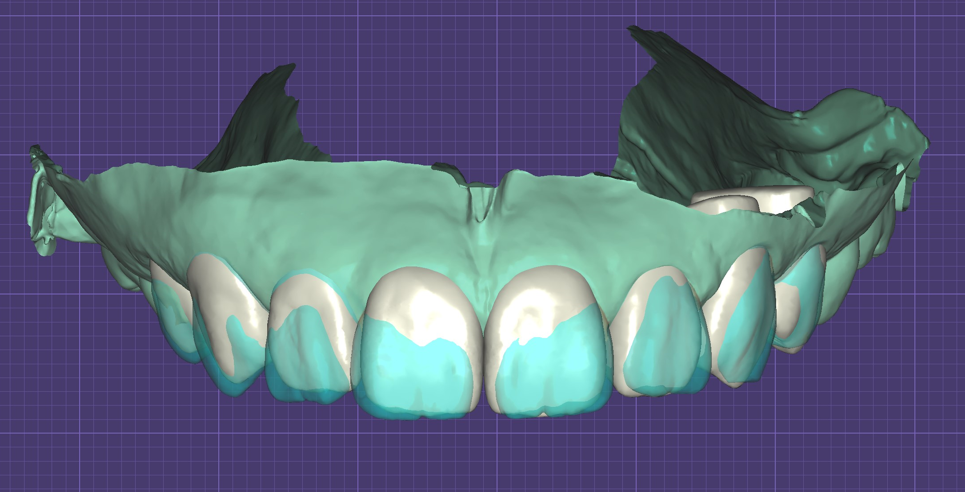

- 光學口腔掃描與電腦3D建模,如同單眼相機與高階攝影設備,精細度高且提供多面向檢視,可以當下確認立體模型正確性,降低誤差;

- 數位建模與模擬調整省去了來回試戴的繁瑣,提升療程效率;

- 軟體大數據分析:從型態資料庫抓取資料,提供病患審美上的參考,讓其依據個人特色做調整,如:兔寶寶牙、小犬牙、微笑曲線等;

吳冠儒牙醫師的衡星診所與寬庭牙醫診所使用德國Cerec 3D數位系統,加上DSD (Digital Smile Design) 微笑曲線設計,先分析臉部與齒型,透過計算對笑容與成品進行模擬,再由診所內配置的牙技師團隊即時製作與調整,一天內將你對笑容的想像完成改造。

正規且美觀的牙齒貼片是透過一系列嚴謹且系統化的流程所製作出來,從詳細討論、攝影和口腔掃描開始,經過精密計算進行牙齒與笑容的模擬與細部調整,最後用齒雕機做出成品。